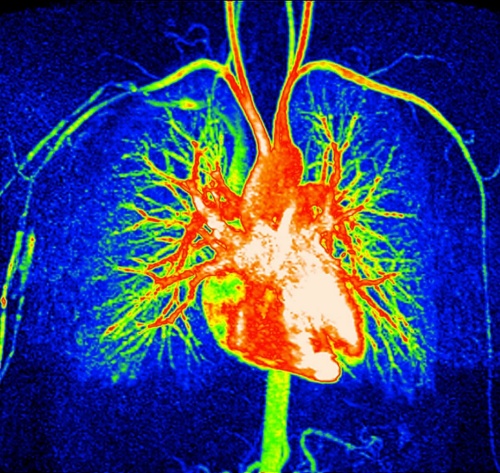

磁気共鳴血管撮影法(MRA)によって映し出された心臓周辺の複雑な血管ネットワーク。植物性食品中心の食生活は、血圧を下げ、悪玉コレステロールを減らし、心血管疾患のリスクを下げることで心臓の健康の改善につながることが、研究によって示唆されている。(Photograph by Zephy/Science Photo Library)